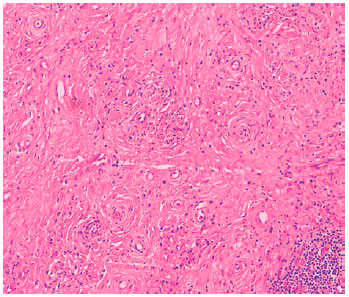

Biopsies of the nasal polyps were performed. Pathological findings revealed characteristics typical of EAF (Figure 2). No IgG deposits were visible on immunofluoroscopy.

IHP has recently been associated with IgG4-RDs(2-5,13). It has been postulated that IgG4-RDs may account for a substantial subset of patients who were previously classified as idiopathic. The definitive diagnosis of IgG4-RD requires histological confirmation; however, in this case, the patient refused to undergo meningeal biopsy. EAF is a rare condition which is usually classified as a type of IgG4-RD(10,13). The present case did not present typical histopathological signs of IgG4-RD in the nasal polyps biopsy. Moreover, serum IgG4 levels were normal. Therefore, we cannot consider this case to be associated with IgG4. To the best of our knowledge, this is the first report of IHP associated with EAF.